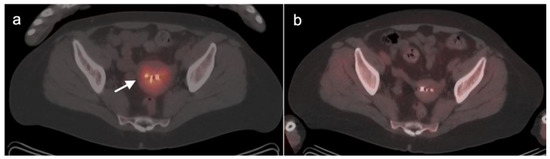

2.6. Vulvar Carcinoma